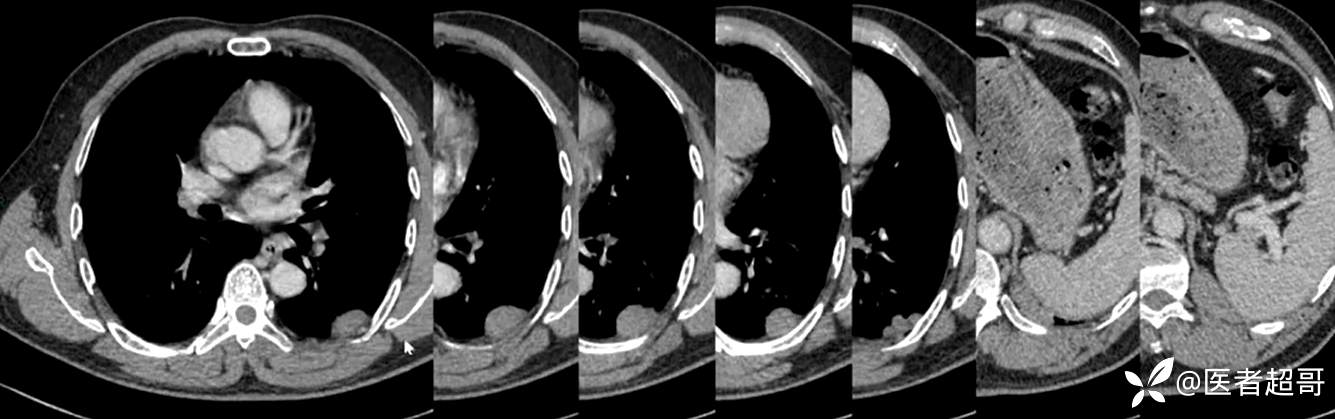

现病史:患者5月前因咳嗽、咳痰于当地医院就诊,完善胸部CT提示:胸膜多发占位,期间患者无胸闷、气紧、咳嗽、咳痰、心慌等不适,患者于我院门诊行胸部CT提示:左下胸膜增厚并见多个软组织密度结节影局限性凸起,较大者大小约3.5x2.2cm,增强扫描呈持续性轻度强化,考虑肿瘤性病变可能性大;门诊遂以:胸膜肿瘤收入我科。